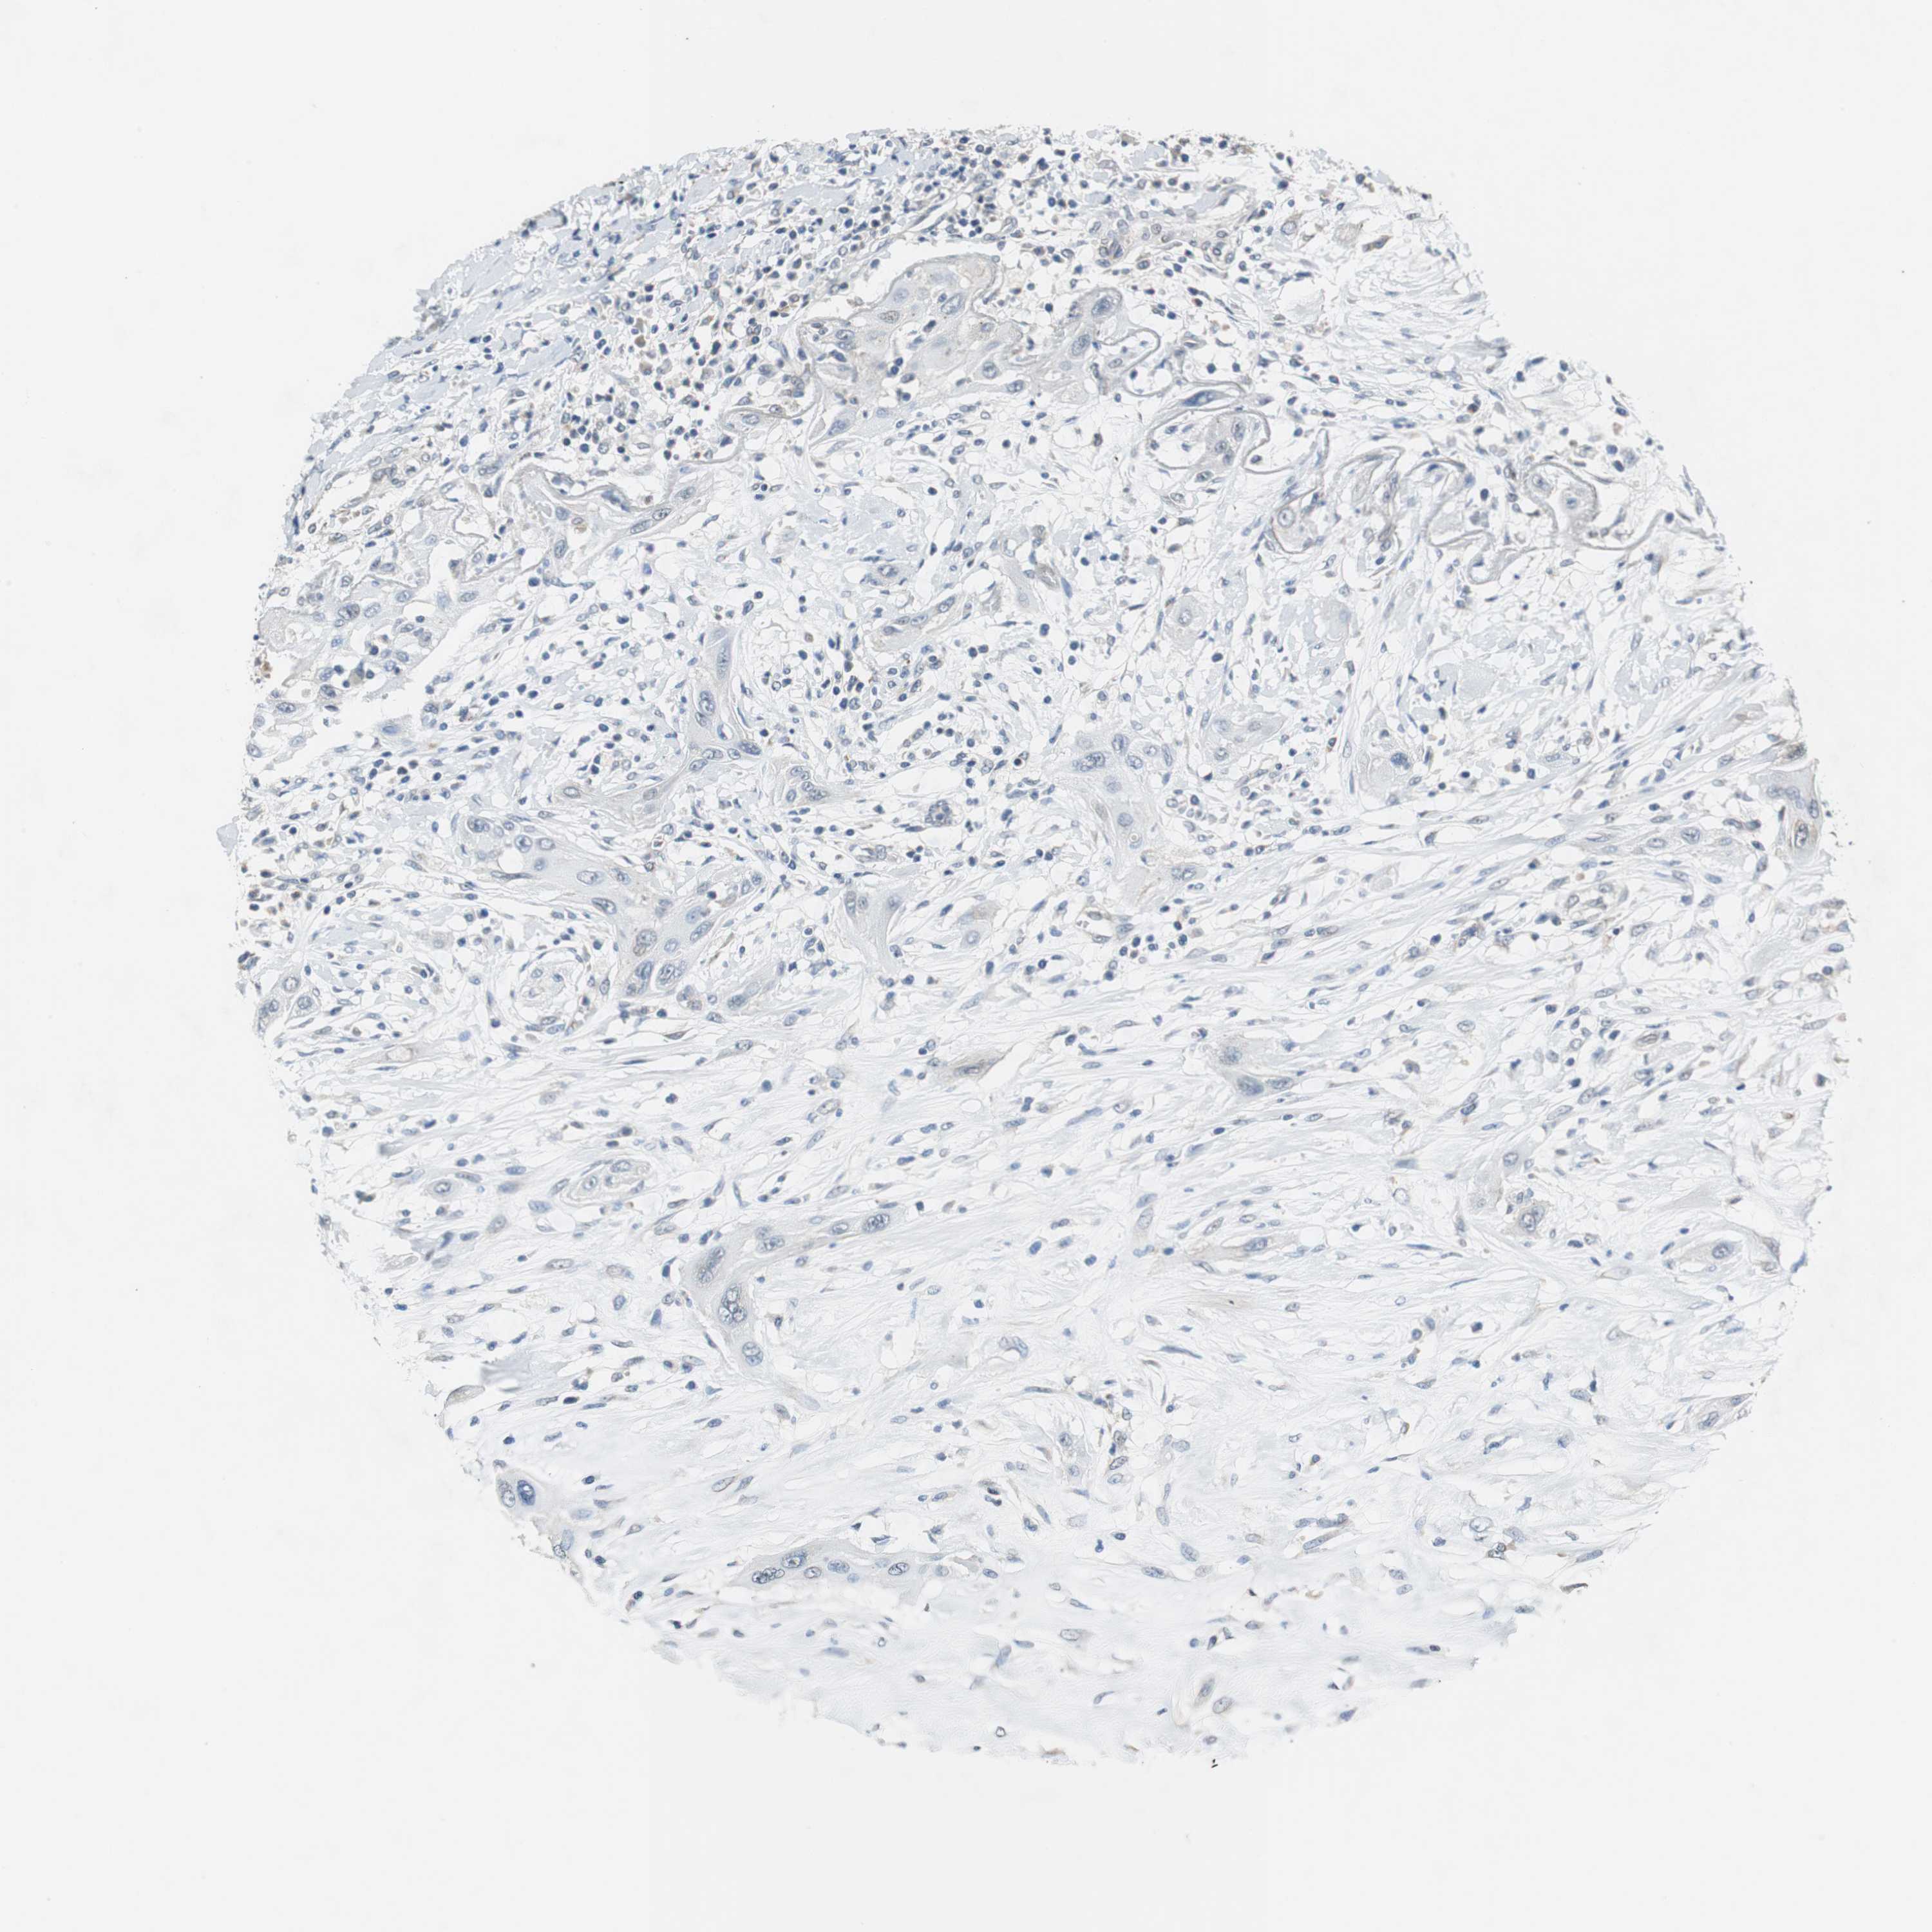

LUNG SQUAMOUS CELL CARCINOMA (TCGA) - Interactive survival scatter ploti

The Survival Scatter plot shows the clinical status (i.e. dead or alive) for all individuals in the patient cohort, based on the same data that underlies the corresponding Kaplan-Meier plots. Patients that are alive at last time for follow-up are shown in blue and patients who have died during the study are shown in red.

The x-axis shows the expression levels (FPKM) of the investigated gene in the tumor tissue at the time of diagnosis. The y-axis shows the follow-up time after diagnosis (years). Both axes are complimented with kernel density curves demonstrating the data density over the axes. The top density plot shows the expression levels (FPKM) distribution among dead (red) and alive patients (blue). The right density plot shows the data density of the survived years of dead patients with high and low expression levels respectively, stratified using the cutoff indicated by the vertical dashed line through the Survival Scatter plot. This cutoff is automatically defined based on the FPKM cutoff that minimizes the p-score. The cutoff can be changed by dragging the vertical line or by entering a cutoff value in the square labeled "Current cut-off".

Under the Survival Scatter plot the p-score landscape (black curve; left axis) is shown together with dead median separation (red curve; right axis). Dead median separation is the difference in median mRNA expression between patients who have died with high and low expression, respectively. It is calculated as follows: median FPKM expression of dead patients with high expression - median FPKM expression of dead patients with low expression. This is intended to aid the user in visually exploring custom cutoffs and the associated p-scores and dead median separation.

Individual patient data is displayed and can be filtered by clicking on one or more of the category buttons on the top of the page. Categories describing expression level and patient information include: high, low, alive, dead, female, male and tumor stages. The scale of the x-axis can be toggled between linear and log-scale by clicking on the "x log" button. Mouse-over function shows TCGA ID, patient information and mRNA expression (FPKM) for each patient.

& Survival analysisi

Kaplan-Meier plots summarize results from analysis of correlation between mRNA expression level and patient survival. Patients were divided based on level of expression into one of the two groups "low" (under cut off) or "high" (over cut off). X-axis shows time for survival (years) and y-axis shows the probability of survival, where 1.0 corresponds to 100 percent.

CNOT3 is not prognostic in Lung Squamous Cell Carcinoma (TCGA)

Best expression cut offi

Based on the FPKM value of each gene, patients were classified into two groups and association between prognosis (survival) and gene expression (FPKM) was examined. The best expression cut-off refers the FPKM value that yields maximal difference with regard to survival between the two groups at the lowest log-rank P-value. Best expression cut-off was selected based on survival analysis .

When clicking on this number, the vertical dashed line indicating cut-off, the interactive survival plot, and the Kaplan-Meier curve will be adjusted to show results based on the best expression cut-off.

: 29.34

P scorei

Log-rank P value for Kaplan-Meier plot showing results from analysis of correlation between mRNA expression level and patient survival.

N/A

5-year survival highi

5-year survival for patients with higher expression than the expression cutoff.

For melanoma and glioma, 3-year survival is shown.

5-year survival lowi

5-year survival for patients with lower expression than the expression cutoff.

TCGA RNA samplesi

RNA-seq data is reported as average FPKM (number Fragments Per Kilobase of exon per Million reads), generated by the The Cancer Genome Atlas (TCGA) .

Normal distribution across the dataset is visualized with box plots, shown as median and 25th and 75th percentiles. Points are displayed as outliers if they are above or below 1.5 times the interquartile range. FPKM values of the individual samples are presented next to the box plot.

Average pTPM 31.7

Number of samples 489